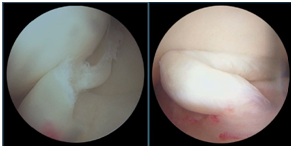

半月板损伤怎么样来修复呢,手术怎么做呢?

手术是通过关节镜来进行的,是非常微创的手术。一般两个小于1cm的切口就可以解决了。大部分患者仅适用两个小于1cm的切口,而且位于膝眼位置,

不仔细看看不出来。利用关节镜技术把损伤的半月板修整缝合加固。